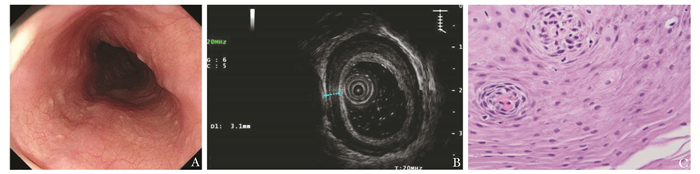

• 摘要: 本文报道一例因吞咽困难而就诊的嗜酸性粒细胞性食管炎病例。该患者为54岁女性,超声胃镜可见食管弥漫性增厚,病理示食管鳞状上皮内散在嗜酸性粒细胞浸润伴嗜酸性粒细胞微脓肿形成,嗜酸性粒细胞计数密度约为30个/HPF,符合嗜酸性粒细胞性食管炎的诊断标准(中度活动性)。口服醋酸泼尼松30 mg/d并逐步减量后,患者临床症状明显减轻,且影像学证实病变具有明显改善。本文总结该患者的诊疗经过并结合文献进行深入剖析,以期提升临床医生对该病的认知。

Abstract: This paper reports a case of eosinophilic esophagitis who presented with dysphagia. The patient was a 54-year-old woman with diffuse esophageal thickening on ultrasonographic gastroscopy. Pathology demonstrated scattered eosinophilic infiltration within the squamous epithelium of the esophagus, accompanied by eosinophilic microabscess, and the counting density of eosinophilic cells was about 30/HPF, which was consistent with the diagnostic criteria of eosinophilic esophagitis (moderately active). After oral administration of prednisone acetate 30 mg/d and gradual reduction of the dose, the patient's clinical symptoms were significantly eased, and the imaging confirmed the improvement of the lesions. This article summarizes the patient's diagnostic and therapeutic process, and reviews the relevant literature in order to enhance clinicians' understanding of this disease.